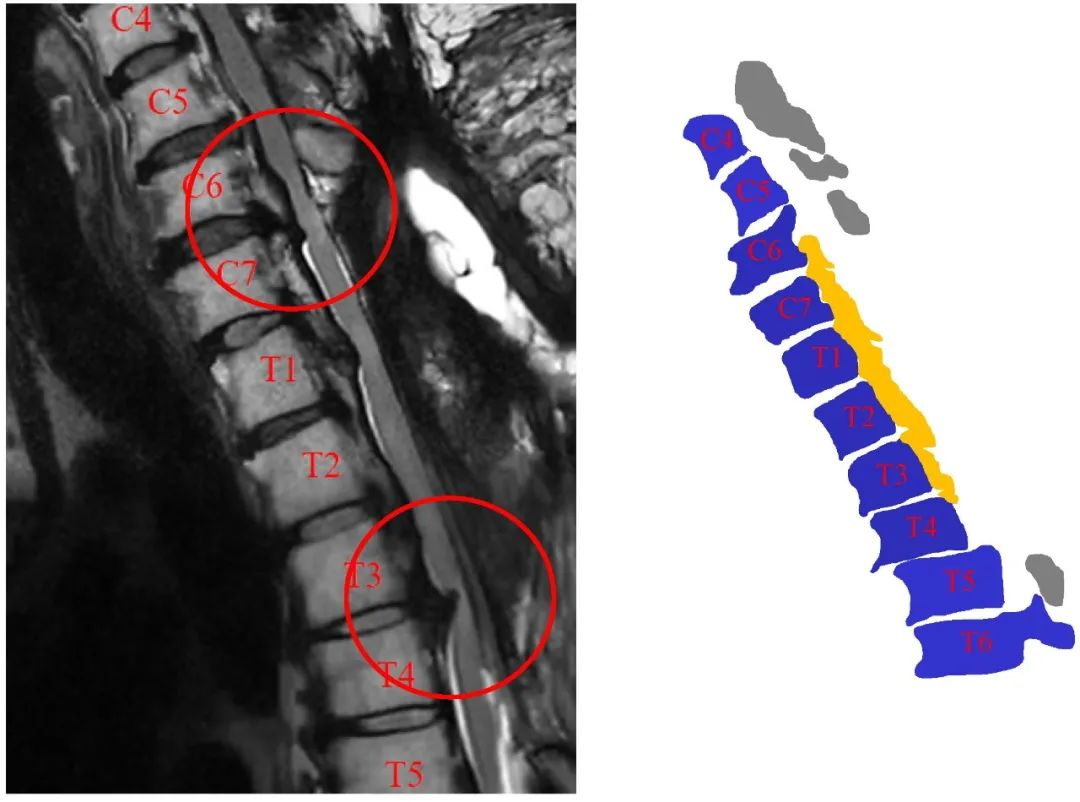

病史:M, 34 y/o

Present History:

Numbness of right lower limb for 2 months, weakness for 1 week

Urination disorder

Past History(-):

Body Weight: 120Kg; BMI: 39.5

影像资料:

诊断&治疗:

Thoracic spinal stenosis(T2-T3)

Thoracic spinal stenosis decompression(T2-T3)